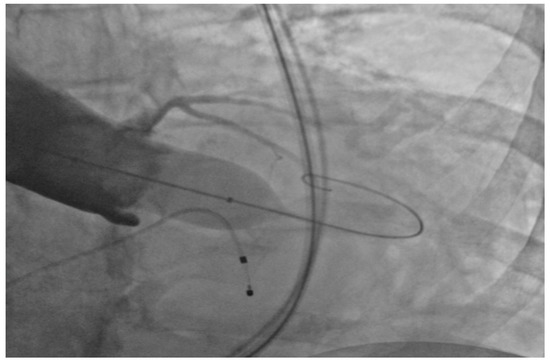

Under general anesthesia, the right and left femoral arteries were each accessed with 6-french sheaths. A temporary pacemaker was placed in the right ventricle through an 8-french sheath in the right femoral vein. Balloon valvuloplasty was performed by advancing a balloon via the right femoral artery sheath, and during rapid ventricular pacing at 160 beats per minute, inflating it across the aortic valve to clear the stenosis and to deploy the 26-mm SAPIEN S3 bioprosthetic aortic valve (Figure 1), which expanded within the native aortic valve (Figure 2). The purpose of rapid ventricular pacing during TAVI is to reduce cardiac output, which facilitates balloon inflation across the valve and placement of the bioprosthetic aortic valve. The mean valvular gradient after TAVI decreased to 1.9 mm Hg (normal is <5 mm Hg). There were no intraoperative complications. The patient was extubated and transferred to the coronary care unit with the temporary transvenous pacemaker, which was removed two days later.

Figure 1.

Balloon inflation across the aortic valve.